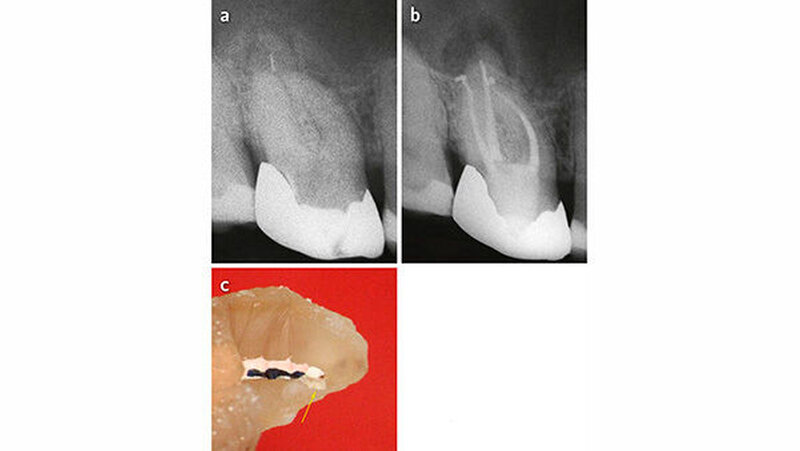

In einer Nachfolgeuntersuchung zu unserer eigenen Studie stellte Helbling (2014) fest, dass es keinen Unterschied bezüglich des klinischen Erfolgs nach ≥ 3 Jahren gab, wenn das frakturierte Instrument nicht vollständig entfernt werden konnte und/oder es anlässlich des Entfernungsversuchs zur Perforation gekommen war, verglichen mit Zähnen mit erfolgreicher Instrumentenentfernung (Abb. 4 und 5). Das Untersuchungsgut lässt außerdem die Vermutung zu, dass die Stärke der Kanalkrümmung die Erfolgswahrscheinlichkeit bezüglich Instrumentenentfernung beeinflusst. Wegen der kleinen Anzahl der Fälle sind diese Ergebnisse jedoch nicht abschließend.